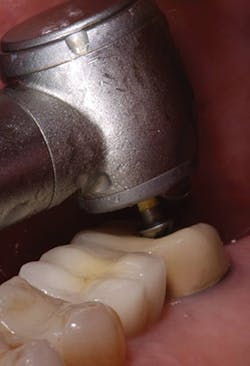

My first step in treatment was to create an access hole in the central fissure, where I then inserted a 2 mm reduction bur (Kometas, www.occlusalbur.com). In my opinion, this is the only way to guarantee adequate reduction to a tooth during preparation (Fig. 3). As you can see in Fig. 4, there does appear to be adequate clearance from a side view. However - and I cannot emphasize this enough - there is a significant difference between occlusal clearance and occlusal reduction. Fig. 5 clearly shows the preparation mark remaining following penetration with the 2 mm reduction bur mentioned previously. Following final preparation, another photo was taken from the side showing the preparation following adequate reduction (Fig. 6).

FIG. 4